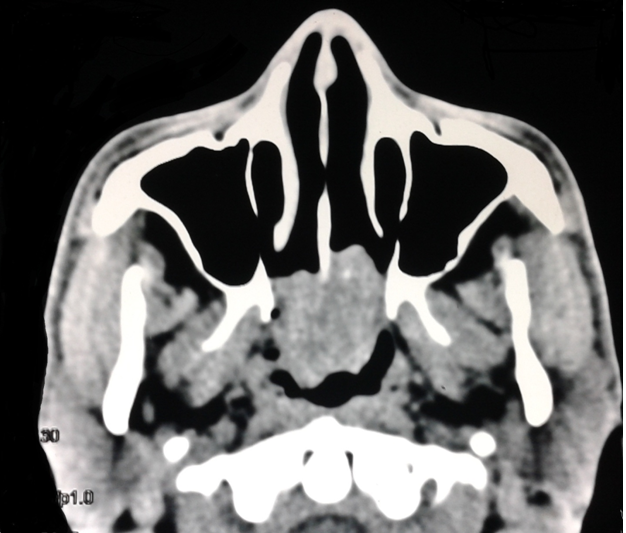

A 25year old man presented with history of progressive bilateral nasal obstruction and snoring for the past two years. There was no history of nasal discharge, post nasal drip, nasal bleeding and his wife reported difficulty in sleeping in the same room with the patient due to snoring. Anterior rhinoscopy was normal. On diagnostic nasal endoscopy a lobulated mass arising from the superior aspect of posterior septum on left side, obstructing whole of the choana was seen (Figure 1). Computed tomography revealed a soft tissue mass occupying whole of the nasopharynx abutting the nasal septum (Figure 2). Paranasal sinuses were normal. Patient was taken up for endoscopic excision and biopsy. Local anesthesia was infiltrated in the pedicle and the stalk of the polyp was resected with the small amount of normal surrounding mucosa. The base of the stalk was cauterized with bipolar cautery. No nasal packing was required and patient was discharged on the same day. Macroscopically the mass was of around 5X2X2cm with lobulated surface and multiple firm nodules were palpable over the surface (Figure 3). On cut section white strands were found, along with few cystic areas (Figure 4). Histopathology revealed a polypoidal tissue mass with marked inflammatory infiltrate containing mostly lymphocytes with lack of Stromal edema and goblet cell hyperplasia; these were suggestive of fibroinflammatory polyp. Postoperative period was uneventful. There was no recurrence in the six months follow up.

Figure 1 Endoscopic photograph on left side showing the polyp filling the posterior choana and its attachment on the superior aspect on posterior septum.